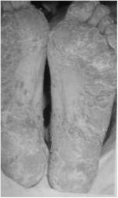

1.4.1.5.1一、症状及体征